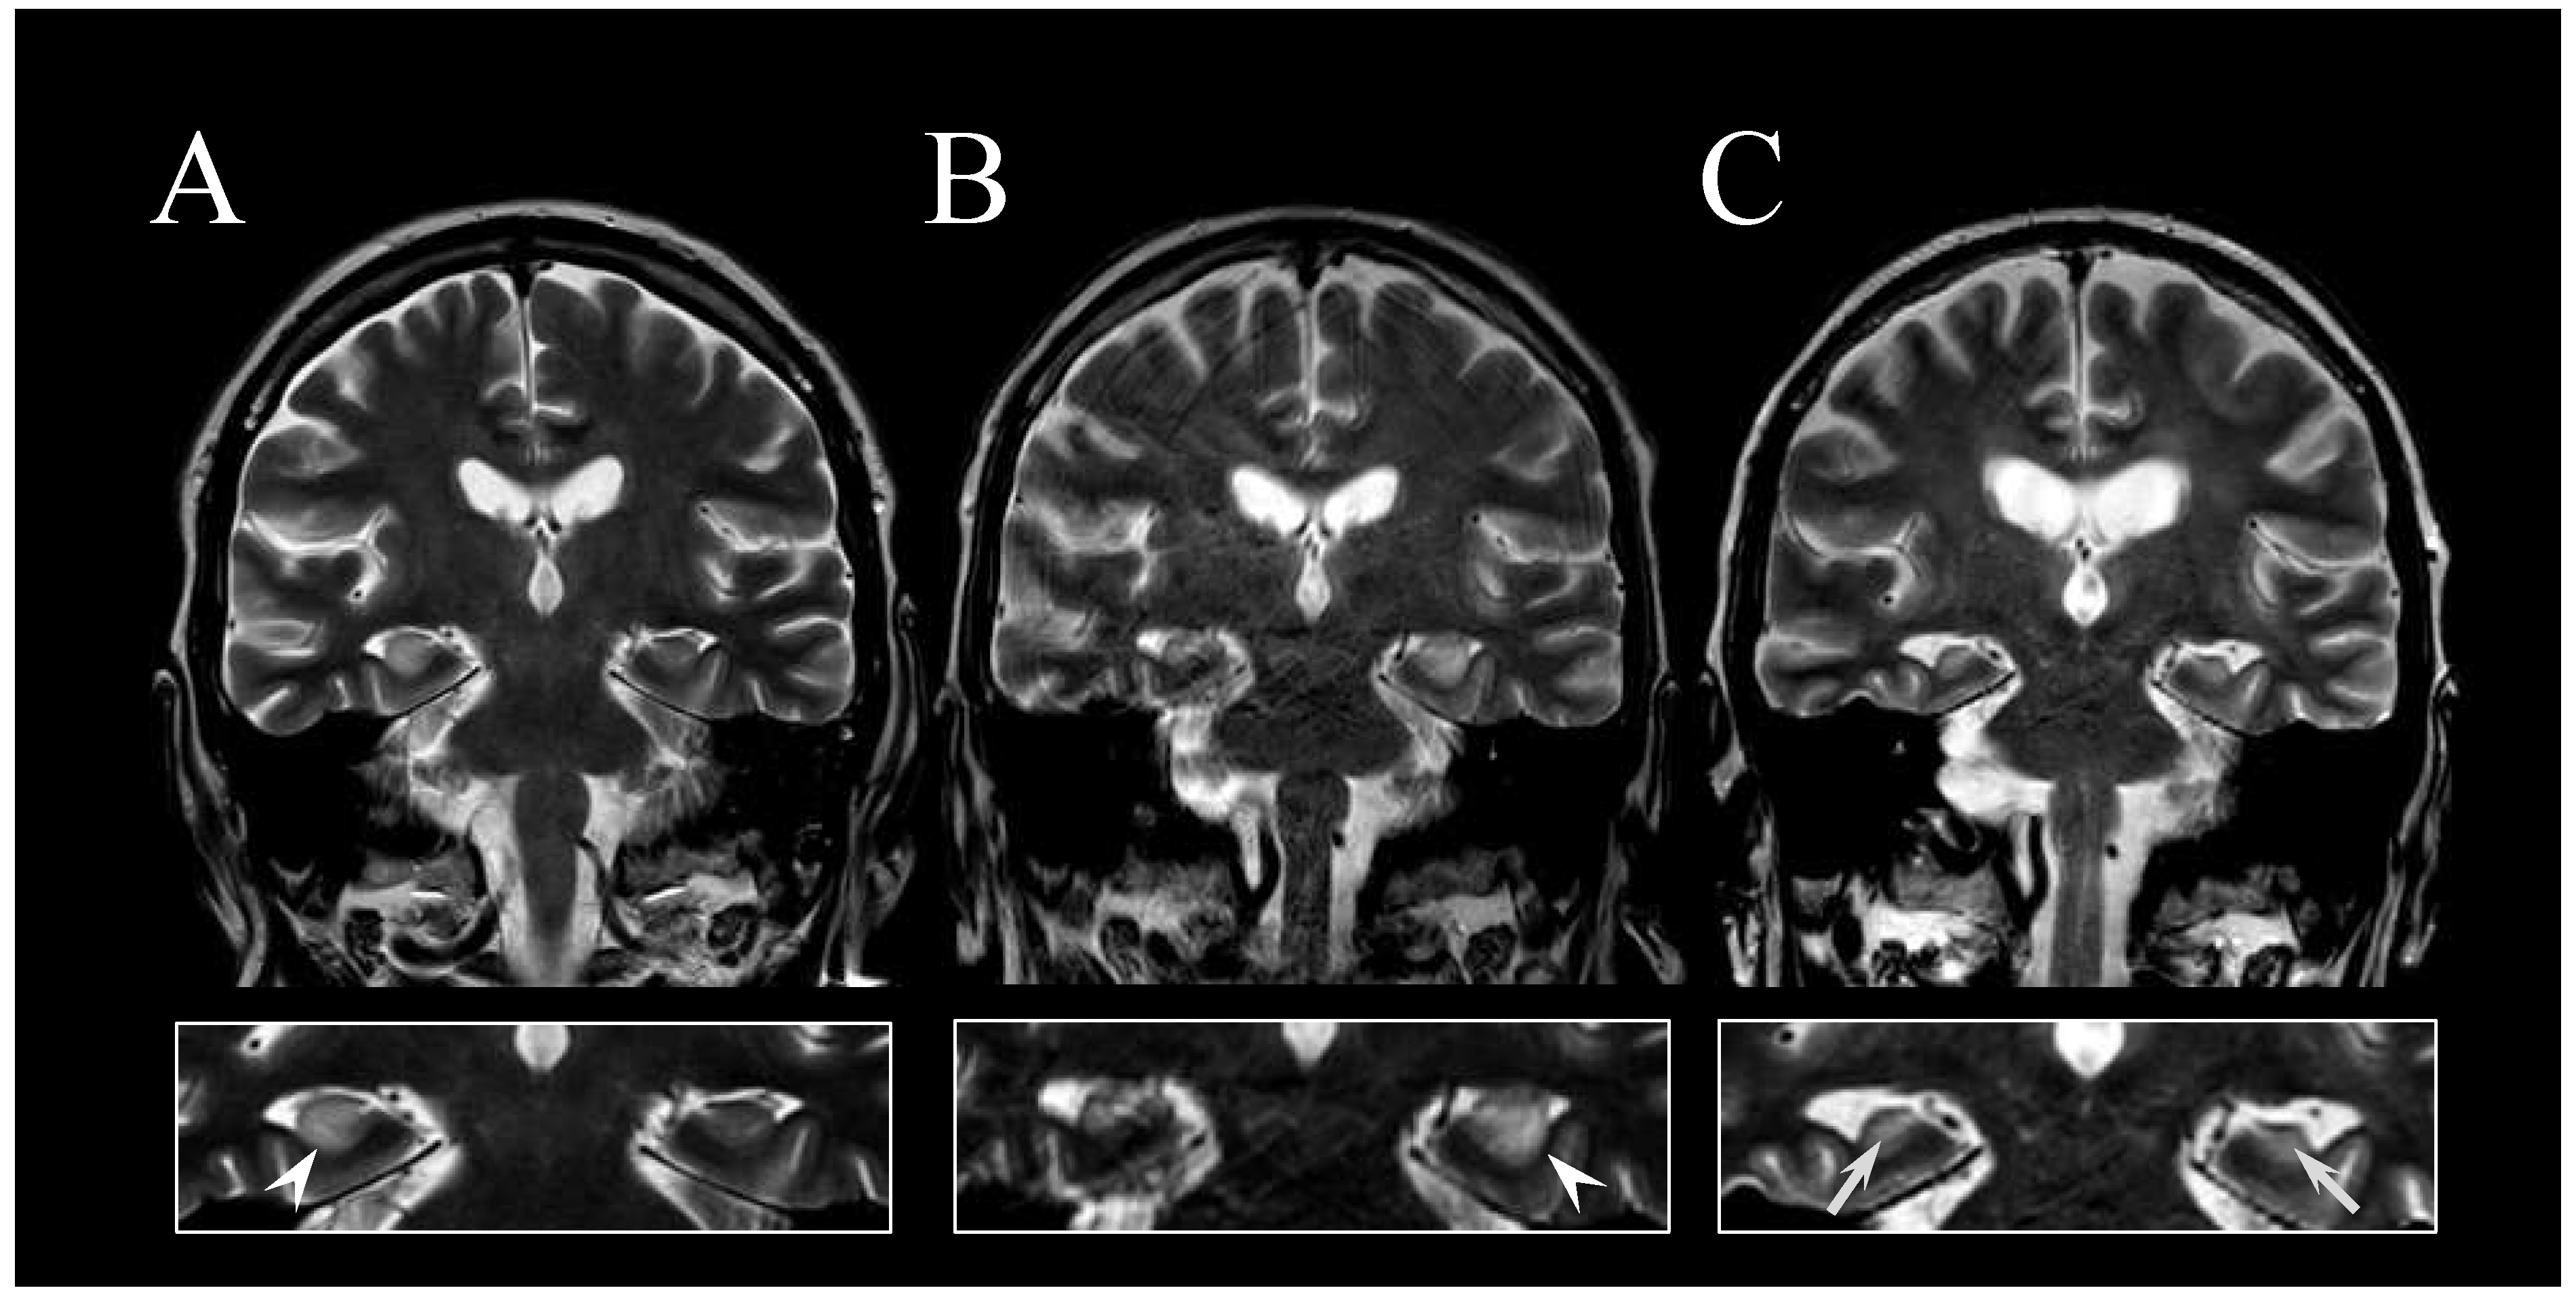

2. Case Report